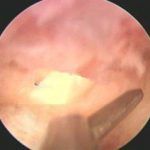

宫腔粘连检查动态数字化子宫输卵管造影 2020/04/10 分类:宫腔粘连 1208 0动态数字化宫腔子宫输卵管造影(HSG)能明确宫腔粘连,但是无法显示子宫内膜纤维化及稀疏的粘连带。 标签:宫腔粘连检查 上一篇: 宫腔粘连病因多与刮宫有关系 下一篇: 宫腔粘连全景彩超检查